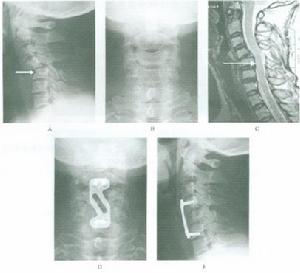

圖1 屈曲暴力雙側小關節脫位形成上下關節突對頂狀態本病多見於高處跌落,頭頸部撞擊地面,或重物直接襲擊,致枕頸部受到屈曲性暴力作用。揮鞭樣損傷也可造成脫位。在乘坐高速行駛的車輛聚然剎車時,頭頸部因慣性作用則猛烈屈曲。當頭頸部遭受屈曲暴力時,頸椎活動單位的支點位於椎間盤中央偏後部。由於頸椎的小關節突關節面平坦,且與水平面呈45°交角,驟然屈曲的外方,引起上位頸椎的下關節突前移並將關節囊撕裂,而後向後上方翹起。隨著外力的繼續作用和頭顱重量的慣性作用,已移位的下關節突繼續向前滑動,整個上位椎體也隨之前移。作用力消失後,因頸部肌肉收縮作用,可形成三種狀態:一是隨之復位,日後可有頸椎不穩症或傷後呈半脫位狀態;二是頸椎脫位呈彈性固定,上下關節突關節相互依託,形成頂對頂的“棲息”狀態(圖1);三是上位椎體下關節突越過了下方椎體的上關節突,形成小關節突背靠背的形態,即所謂的“交鎖”狀態。

圖1 雙側關節突脫位X線特徵本病的檢查方法主要有以下兩種:

1、X線檢查

側位X線片典型徵象為:脫位的椎體向前移位的距離為椎體前後徑的2/5,上位頸椎的下關節突位於下位頸椎上關節突的頂部或前方,兩棘突間距離增大(圖1)。前後位片可見鉤椎關節關係紊亂,小關節相互關係顯示不清。斜位片顯示神經孔變形。斷層攝影更有利於診斷。